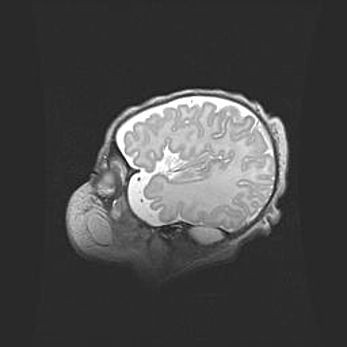

Неполная лизэнцефалия (пахигирия). Открытая гидроцефалия.

Возраст: 17 дней

Вес: 3110 г

Пол: мужской

Окружность головы: 33,5 см

Срок гестации: 35-36 недель

Лизэнцефалия—недоразвитие корковой пластинки и мозговых извилин в результате нарушения миграции нейронов коры. Поверхность мозговых полушарий гладкая. Микроскопически выявляется отсутствие нормальных слоев коры и скопление групп нейронов в подкорковом белом веществе.

Пахигирия—уменьшение числа вторичных извилин. В пораженном полушарии нервные клетки образуют толстый недифференцированный слой с неправильно расположенными нервными волокнами и группами гетеротопных клеток. Нервные клетки незрелые. Белое вещество истончено. При этом нередко аномально развит корково-спинномозговой путь.